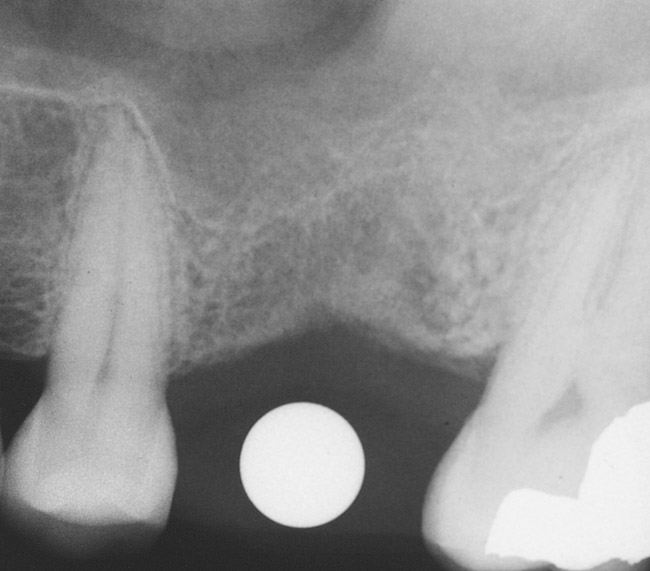

The 2-mm twist drill is used to create an osteotomy 1 mm short of the subantral floor. If any resistance is detected prior to reaching the 3-mm depth, drill penetration must be stopped, because the subantral cortical bone has possibly been reached. Any uncontrolled "push" would penetrate the bone and likely perforate the sinus membrane. A guide pin is then inserted and a radiograph taken to determine if drill penetration has terminated within 1 mm of the subantral floor (Figure 2). If the radiograph indicates that more than 1 mm of bone is present subantrally, the twist drill is used again to penetrate within 1 mm of the sinus floor. Alternately, an osteotomy tip for a piezosurgery unit can be used for this purpose. The final depth of penetration should be verified with another periapical film.

Figure 2  After drilling to a depth of 3 mm with a 2.1-mm twist drill, the guide pin was placed and a radiograph was taken to ascertain if the drill stopped within 1 mm of the subantral floor.

Figure 2